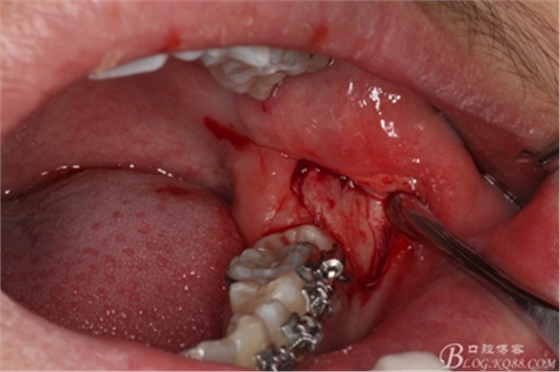

圖9.高速拔牙手機(jī)去骨

圖10.去骨后暴露出38的牙冠

圖11.縱分牙冠